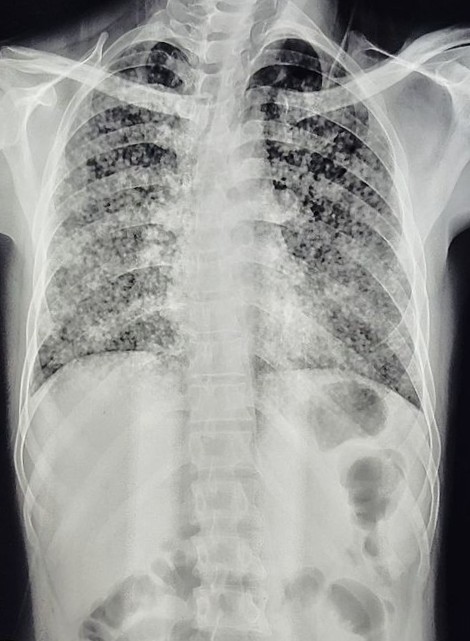

| 220 | IGGMC, Nagpur, Nagpur | P2 | 29-4252 | AMOL PAUNIKAR | Consent taken on Paper | 36 Yrs. |

Provisional Diag : BILATERAL INFILTRATION ? MILLIARY TB

Final Diag : MILLIARY TB |

TB Case (Confirmed) | MILLIARY TB | Abnormality visible on x-ray |

View |

|||